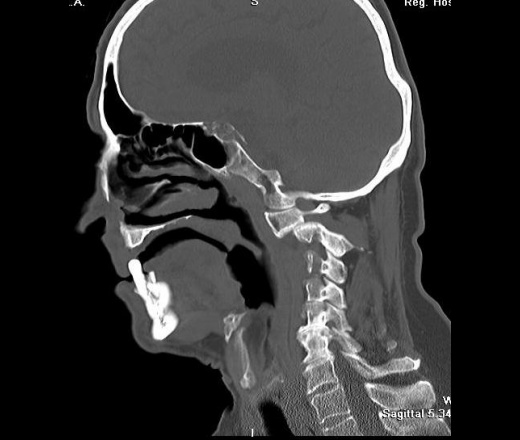

Мужчина, весьма преклонного возраста, обратился на прием в поликлинику в сопровождении родственников. Предъявляет жалобы на головную боль, плохую память, Направлен неврологом на КТ головного мозга.

Но были обнаружены изменения, и в шее, которые, явились случайной находкой. Анамнез собрать было проблемно, с памятью у пациента - "совсем плохо". Родственники отмечают (мужчина живет один в деревне), что несколько месяцев тому мужчина упал и разбил голову, было много крови.

Перелом основания зуба С2 со смещением вперед....

Главная опасность - это сужение позвоночного канала между фрагментами позвонков. Поперечное сечение спинного мозга на уровне шеи около 13 мм, если расстояние меньше, как в этом случае, - возможна быстрая гибель спинного мозга...

Сначала было исследование головного мозга, от С1 до макушки. Мне не понравилась "теснота" в задней черепной ямке, т. е. суженные субарахноидальные щели, и это на фоне атрофиченских изменений. Взглянув на боковую топограмму, решила сделать и шею. На тот момент указаний на травму не было. Только попытав дочь пациента удалось установить факт травмы. Парезов и параличей нет. Нейрохирурги отправили пациента домой, посоветовали носить воротник.